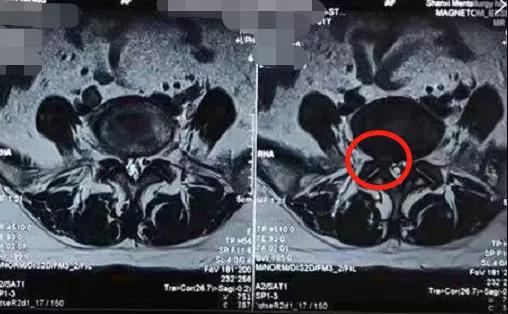

冶金动态|陕西冶金医院80岁股骨粗隆间骨折老人手术后,一周内下床活动。

张老太太,在家里不慎摔倒,家人救起后紧急送至陕西冶金医院。来院时左髋部疼痛、肿胀、活动受限3小时。来院后立马进行了查体以及X线检测,结果显示: 左股骨粗隆间骨折! 来院